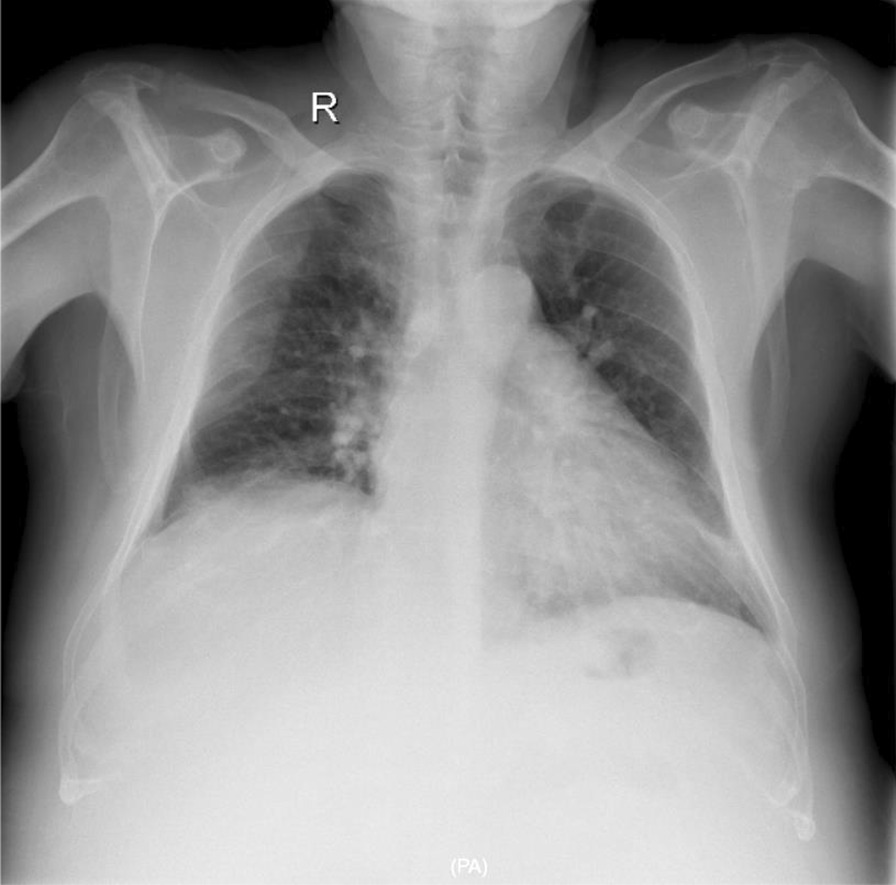

On clinical examination, he was jaundiced, with blood pressure of 90/50 mmHg (baseline systolic blood pressure 120–130 mm/Hg) and heart rate of 72 beats per minute, and he was afebrile (36.7 °C). On skin examination, jaundice and spider angiomata were found on the trunk, face, and upper limbs; gynecomastia was also seen. Neurological examination revealed lethargy, altered mental status, and mild confusion. Neuromuscular impairment was noted including bradykinesia, asterixis (flapping motions of outstretched hands), slurred speech, ataxia, and hyperactive deep tendon reflexes. Focal neurologic deficits were absent. On chest examination, fine crackles were present at the lung bases. The abdominal wall appearance revealed a caput medusae due to portal hypertension, while dilated abdominal veins were also seen because of inferior and superior vena cava syndrome. Physical examination also showed a remarkable abdominal distension, a fluid wave, and flank dullness to percussion, with diffuse tenderness and normal bowel sounds. The liver was palpable two fingers below the right costal margin, with firm and nodular consistency; an enlarged left lobe was also palpable. Peripheral edema was more pronounced at the lower extremities. A chest X-ray performed on admission showed mild bilateral infiltrates of the lower lung areas (Fig. 1). Laboratory parameter values showed increased white blood cell (WBC) count and C-reactive protein (CRP), substantial acute kidney injury, and severe deterioration of liver biochemistry compared to a recent previous evaluation (Table 1).

Fig. 1.

Patient’s chest X-ray on admission